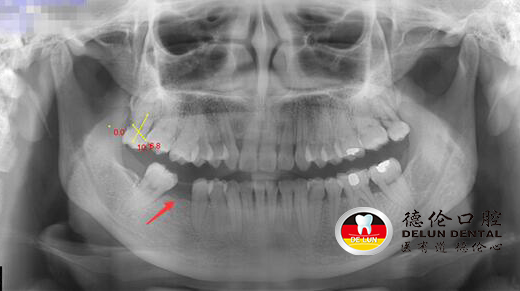

舒女士术前X光照片,下颌缺牙一颗